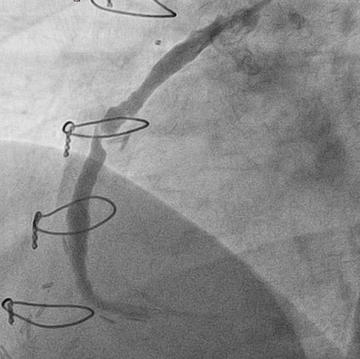

The patient was a 55-year-old man with a subtotal lesion in a 15-year-old SVG to the RCA (Figure 1).

Figure 1: Severe lesion in a large 15-year-old SVG to the RCA